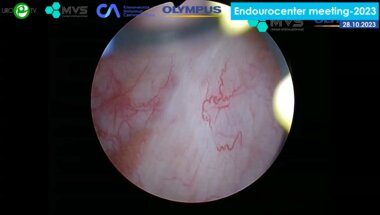

Видео спикера